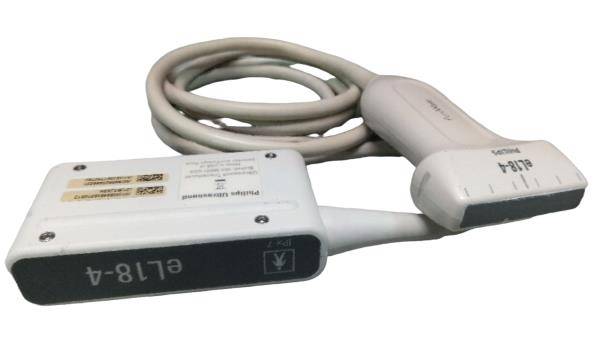

Probe Function: 3.5MHZ convex, abdominal organs

The Ultrasound Scanner utilizes cutting-edge imaging technology, allowing for detailed and accurate evaluations during pregnancy. With capabilities for both convex and transvaginal scanning, this device provides versatile options for healthcare professionals. It is essential for monitoring fetal development and ensuring the health of both the mother and the unborn child. Doctors can easily select the appropriate probe, enabling them to capture high-resolution images that are critical for diagnosis and treatment.